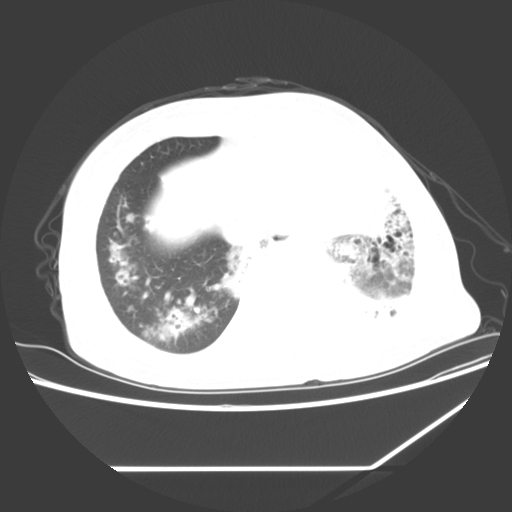

标题: CT25393:病人45岁,咳嗽,吐黄痰带血丝,发热,胸闷月余 [打印本页]

标题: CT25393:病人45岁,咳嗽,吐黄痰带血丝,发热,胸闷月余

1、左肺中央型肺癌并双肺弥漫性转移   2、双肺部感染    3、肺大泡     4、左侧胸腔积液

双侧肺弥漫性病变,可见“空泡征”及“蜂窝征”,考虑肺泡癌可能性大,左侧胸腔积液,考虑胸膜受累可能!

考虑肺泡癌,建议排除感染。

考虑肺泡癌

1)不排除肺泡癌可能。2)左侧胸腔积液。